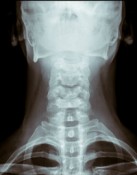

Neck and back injuries range from sprains, strains, fractures, disc injuries, and other spinal injuries. Back injuries may result in significant nerve damage, leaving you with a reduced sensation or control over arms, hands, legs, feet, and other body parts. Suffering spinal damage can leave you permanently disabled. These types of injuries often lead to long-lasting pain and discomfort with ongoing rehabilitation treatment.

Whiplash, a form of soft tissue injury, is caused when the muscles and ligaments in the neck and upper body are stretched due to sudden movements of the head and neck from the car’s impact. This bobbing back and forth is referred to as a sudden extension or flexion. Symptoms of whiplash include neck or upper back pain or stiffness, shoulder pain or stiffness, headache, dizziness, and burning or itching sensation in the neck, shoulder, or arms.